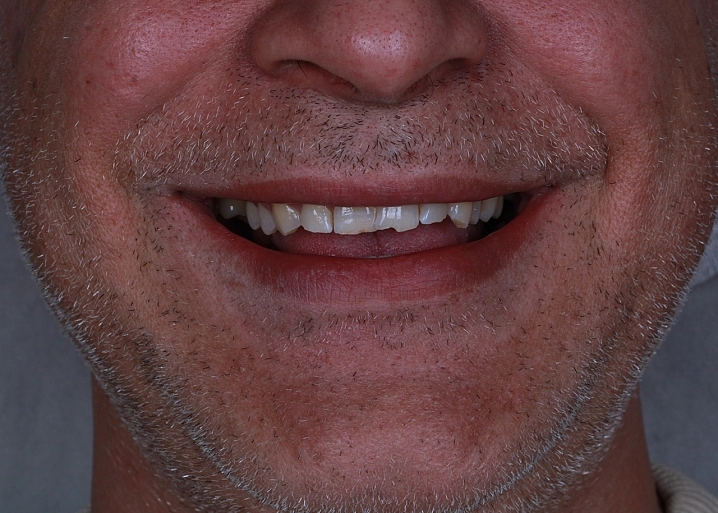

Проведена эстетическая реставрация передних зубов верхней и нижней челюстей винирами E-max. Исправлены форма, размер и восстановлена поверхность зубов.